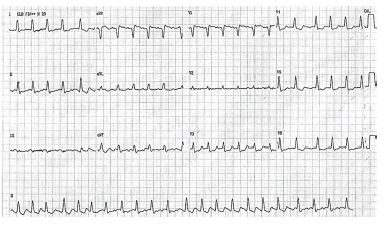

Considere hipoteticamente que paciente do sexo feminino, de 45 anos de idade, chegou ao pronto-socorro com PA de 70 mmHg x 40 mmHg, confusão mental e dispneia. Familiar informa que ela reclamava de sensação de batimentos acelerados e descompassados no coração há seis horas. Ele ainda informa que paciente já apresentou outras vezes episódios de palpitação. Além disso, a enferma tinha sintomas como sudorese, perda de peso, cansaço e dificuldade em dormir há três meses. Paciente não tem histórico de doenças vasculares conhecidas. Posteriormente, foi realizado o ECG.

A respeito desse caso clínico, julgue os itens a seguir.

Deve-se compreender que o que ocasionou a arritmia cardíaca pode ser doença de Graves.

A paciente está com instabilidade hemodinâmica; deve ser realizada cardioversão elétrica sincronizada com 50 J.

Trata-se de uma taquicardia por reentrada nodal, e apresenta como tratamento farmacológico a adenosina IV como opção.